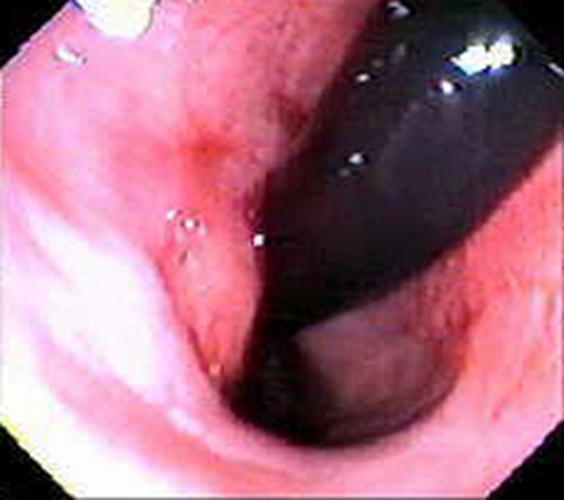

右半結腸癌腺癌浸潤型常見臨床特點

右半結腸癌浸潤型常見臨床 特點